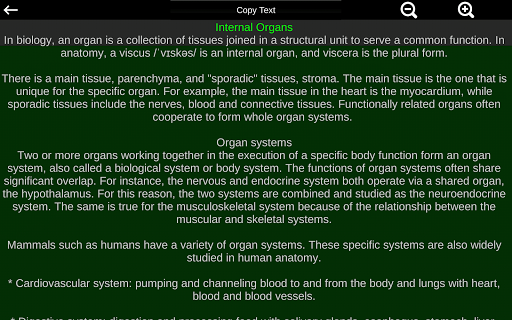

Toont een 3D-anatomisch model van de belangrijkste organen van het menselijk lichaam en een beschrijving van elk orgaan.

* Beschrijvingen van elk orgel.

Deze app is ontworpen als aanvulling op de studie van anatomie in verschillende onderwijs-, gezondheidszorg- en culturele omgevingen.

Praktische, nuttige en waardevolle anatomische informatie binnen handbereik.